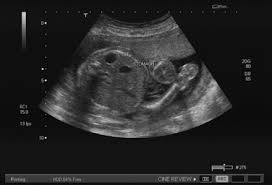

| pic from internet (Iecha punye 1 upper pole only) |

Cyst Merupakan Satu Lubang Yg Trbentuk di Dalam Badan Kite..Ianya Mungkin Berisi Udara Ataupon Cecair. Ape yg Berlaku kt Iecha sayang ialah, Cyst ini Telah Trbentuk Pada Buah Pinggang Sebelah kiri..Ianya Dalam Bentuk Cecair.Kate Doc Cyst ini boleh Berkembang Ataupon Membesar di Dalam Buah Pinggang itu Seiring Dengan Peningkatan Umo Iecha.